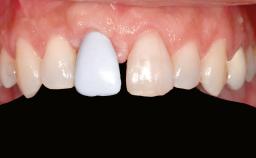

A 47-year-old Caucasian woman with a single-tooth edentulous space at the site of the left maxillary canine was referred for treatment. She had undergone traumatic extraction of this impacted canine several months before referral. Her chief complaint was the dissatisfying appearance of her smile. The patient desired a stable and esthetic rehabilitation of the site. Her dental history showed no evidence of periodontal disease or bruxism. She had no systemic diseases, was not taking any medications, and did not smoke. The extraoral examination revealed a high lip line and an inadequate soft-tissue volume at the defective canine site. Large black triangles were visible between the canine and its adjacent teeth.

Prosthesis Type FDP